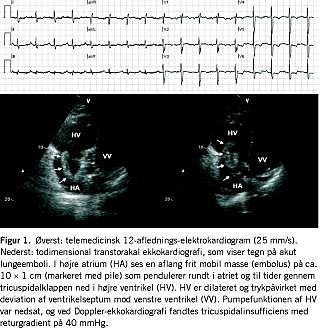

Falck ankom til patientens hjem kl. 11.12 og fandt klinisk, at patienten havde let påvirket respiration, men ikke var alment medtaget. Kl. 11.19 sendte Falck et EKG-12 til Hjertemedicinsk Afdeling B, Skejby Sygehus, da patienten havde nyopstået dyspnø, men ikke kendt astma eller anden kronisk lungesygdom og derfor opfyldte et af kriterierne for at sende et telemedicinsk EKG-12. Kl. 11.24 ringede den telemedicinske læge fra Skejby Sygehus til ambulancen. EKG-12 viste sinusrytme, inkomplet højresidigt grenblok og negative T-takker i prækordialafledningerne (Figur 1A). Blodtrykket var 125/96 mmHg, pulsen 100 min-1 og saturationen 87% uden ilt. På baggrund af EKG-forandringerne, dyspnø, hypoksi, takykardi og synkoper havde den telemedicinske læge mistanke om lungeemboli. Patienten blev visiteret direkte til den lokale hjertemedicinske afdeling 11 km fra hjemmet, og vagthavende læge blev informeret om mistanken. Falck blev informeret om den mulige diagnose og kørte med kørsel 1 til lokalsygehuset med ankomst kl. 12.03.

Her blev der foretaget akut ekkokardiografi, som viste trykpåvirkning af højre ventrikel med en triscuspidalreturgradient på 35-45 mmHg. I højre atrium sås en aflang, frit mobil masse. En akut computertomografiangiografi viste store trombemasser, der startede bilateralt lige før delingen i segmentarterier og strakte sig langt ud i alle grene, hvilket bekræftede diagnosen submassiv lungeemboli [4]. Der var forhøjet D-dimer på 14,3 mg/l. Syre-base-status med 2 l ilt viste nedsat partialtryk af kuldioxid (pCO2) (4,1 kPa) og ilttryk (pO2) (7,6 kPa).

Patienten blev overflyttet akut til Hjertemedicinsk Afdeling B, Skejby Sygehus, til vurdering for akut embolektomi. Der blev foretaget akut ekkokardiografi, som bekræftede diagnosen (Figur 1B). Der forelå ikke kontraindikationer for trombolysebehandling, og efter intern konference mellem overlæger fra Hjertemedicinsk Afdeling B og Thoraxkirurgisk Afdeling T blev der givet behandling med alteplase og heparin. Akut embolektomi blev ikke fundet indiceret. En ekkokardiografi viste tre timer efter behandlingsstart ingen synlige trombemasser, og højre ventrikel var mindre trykbelastet med en reduceret tricuspidalreturgradient på nu 28 mmHg. Klinisk viste effekten sig ved normalisering af pulsfrekvensen til 80 min-1 og aftagende dyspnø. Syre-base-status blev normaliseret under tilførsel af 2,5 l ilt. Patienten blev dagen efter tilbageflyttet til lokalsygehuset til fortsat behandling og udredning for årsagen til lungeemboli. Her blev der påbegyndt peroral antikoagulansbehandling initialt under samtidig behandling med lavmolekylært heparin.